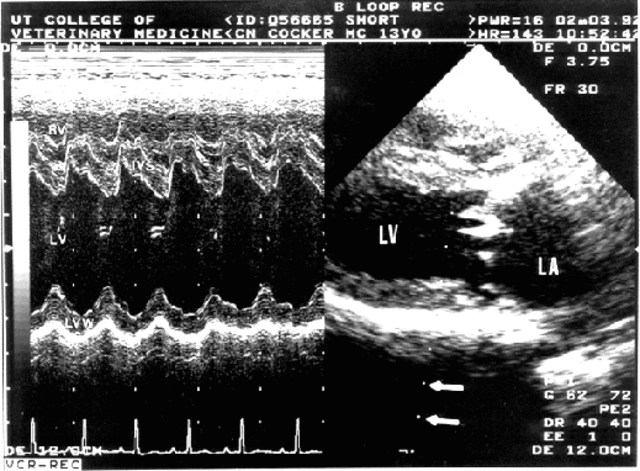

M-Mode Ultrasound

M-mode (Motion) is a method of display in which tissue interface position is displayed along 1 axis and time is displayed along a second axis. M-mode is used to display echocardiographic data in which heart wall motion and valve motion are displayed as functions of time. Reference:

"Ultrasound History." Ultrasound History. N.p., n.d. Web. 05 Apr. 2013.

http://www.radiologytoday.net/archive/rt_120108p28.shtml

http://library.wolfram.com/examples/echocardiogram/Images/index_gr_2.gif

• Development of Echocardiography

Development of Echocardiography

First echocardiogram completed through an echo test conducted from a Siemens shipyard. The ultrasonic pulse-echo technique was first used for nonmilitary purposes for the detection of flaws in metals. Later, this technique was used primarily for the preoperative study of mitral stenosis and diagnosis of mitral regurgitation. Reference: